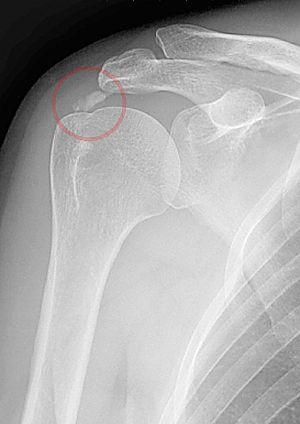

Calcific tendinitis marked.jpg

A plain X ray of the shoulder showing calcific tendinitis

An x-ray showing calcific deposits in the area of the tendons of the rotator cuff muscles

The calcific deposits are visible on X-ray as discrete lumps or cloudy areas. The deposits look cloudy on X-ray if they are in the process of reabsorption, and this is also when they cause the most pain. The deposits are crystalline when in their resting phase and like toothpaste in the reabsorptive phase. However, poor correlation exists between the appearance of a calcific deposit on plain X-rays and its consistency on needling. Ultrasound is also useful to depict calcific deposits and closely correlates with the stage of disease.[6]